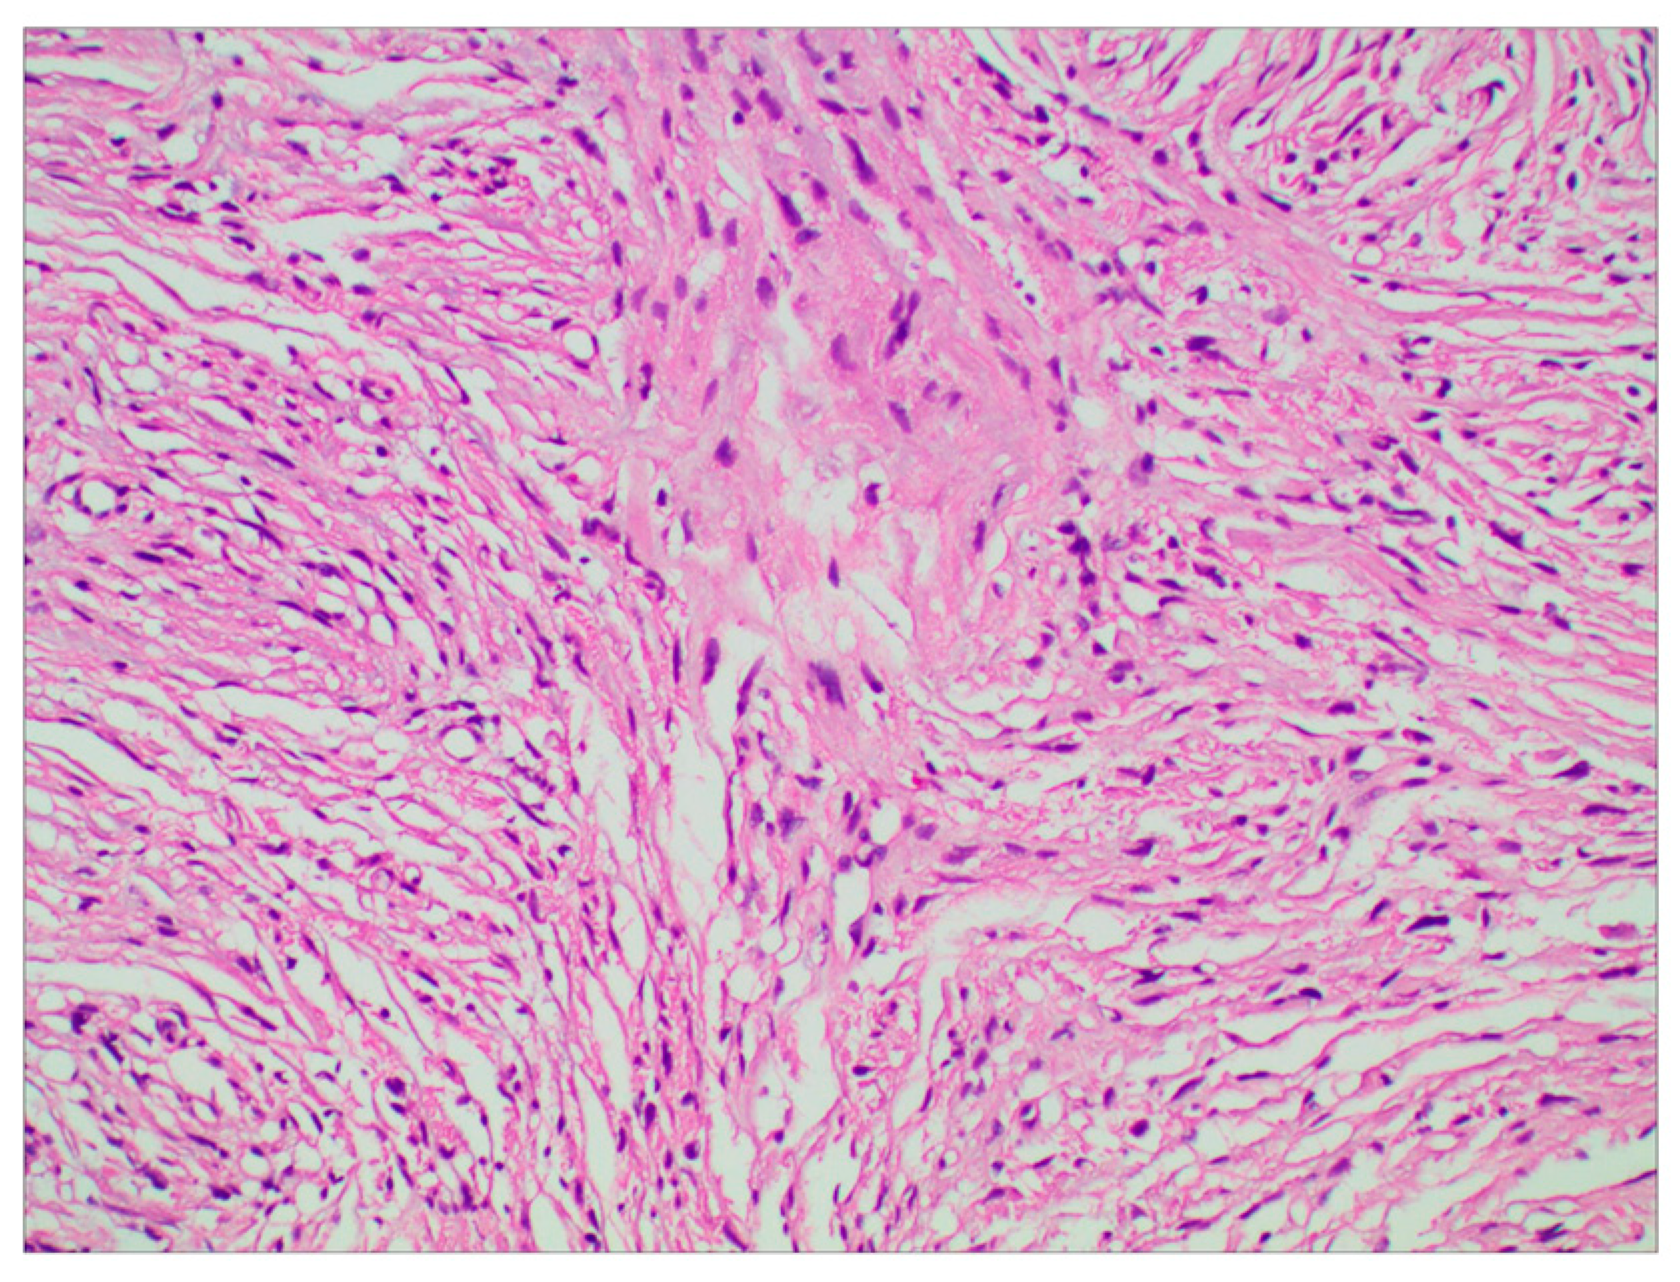

The surgery was uneventful, and the pathological diagnosis was FM, WHO grade I (Figure 3). After surgery, the patient had an uneventful recovery and was discharged with no neurological deficit. The initial clinical follow-up was performed 6 months after surgery, at which point, MRI suggested that the compressed cerebral cortex had returned to its normal form (Figure 4). After 6 months of follow-up, subsequent follow-up visits were performed at yearly intervals or more frequently when indicated. During the 24-month follow-up, the patient’s condition remained favorable, with no tumor recurrence.

Figure 3.

Photomicrographs of tumor specimens demonstrated a fibrous meningioma (H&E staining; original magnification ×200).